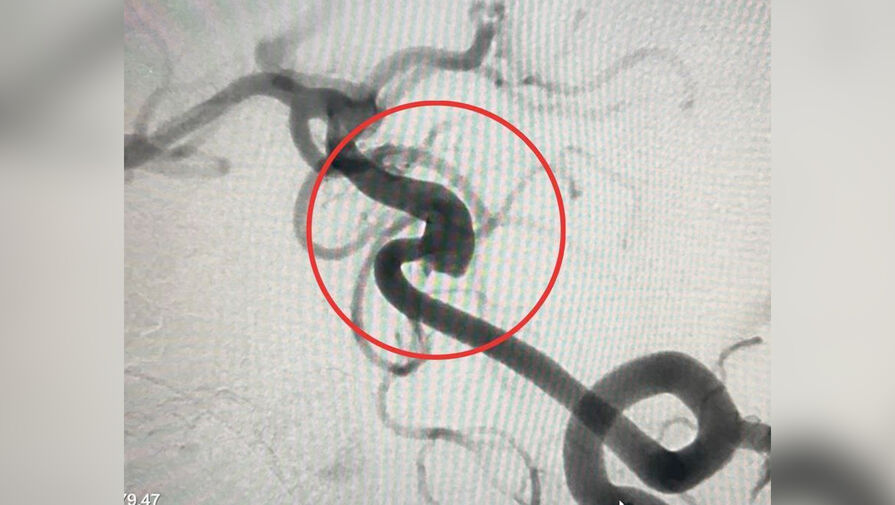

Врачи Детского клинического центра имени Л.М. Рошаля планово прооперировали девятилетнего мальчика с аневризмой в сосудах головного мозга. Об этом сообщили в пресс-службе минздрава Московской области.

Медики отметили, что подобная патология — расширение стенки артерии, отвечающей за кровоснабжение мозга — встречается у детей редко, но требует вмешательства, так как бездействие может привести к кровоизлиянию в мозг.

«В ходе рентгенэндоваскулярного вмешательства, через бедренную артерию мы провели катетер к сосудам головного мозга и разместили имплант в области аневризмы. Операция прошла успешно, нам удалось нейтрализовать возможные риски разрыва, а значит и инсульта», — поделился заведующий отделением рентгенэндоваскулярных методов диагностики и лечения Михаил Комиссаров.